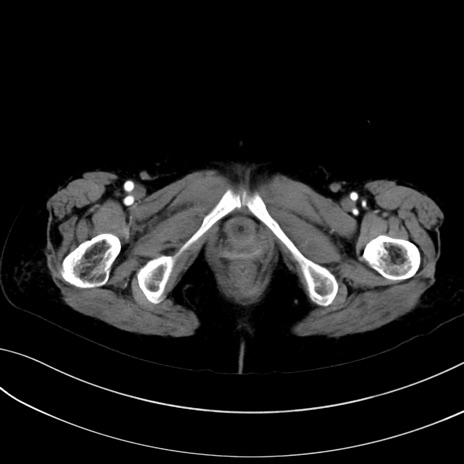

症例13 CT(横断像)1日半後